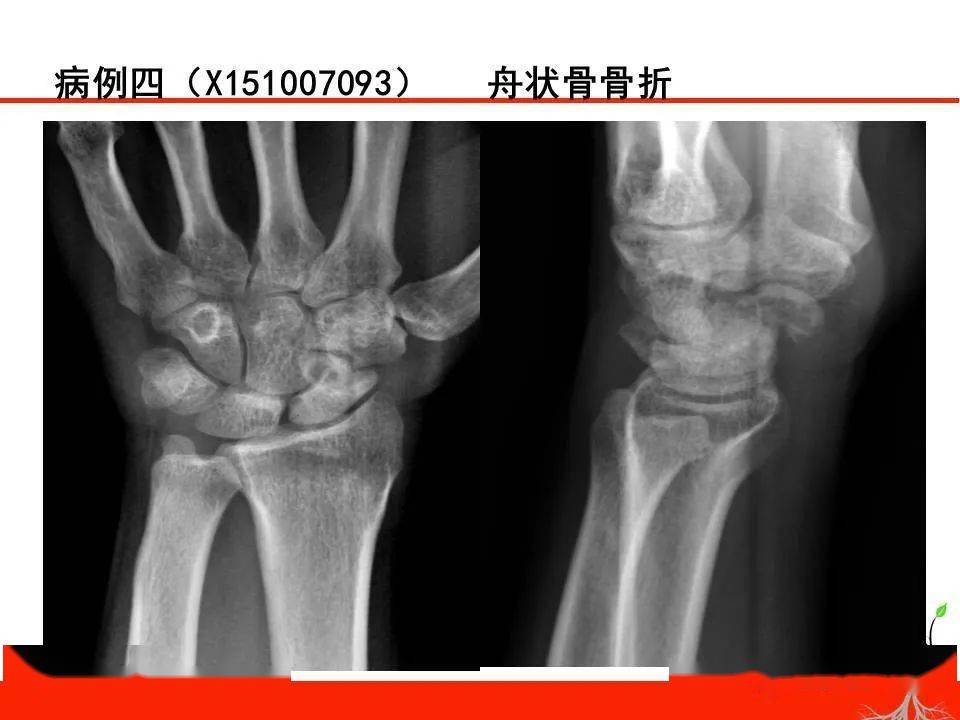

成人腕关节外伤x线诊断